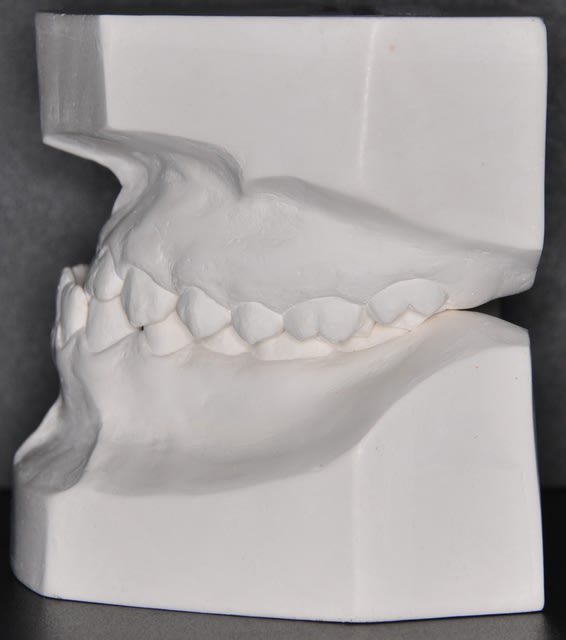

Effectivement, c’est un cas de classe III squelettique à responsabilité maxillaire et mandibulaire, hypodivergent.

Normalement c'est un cas ortho-chirurgical, mais le patient n'a pas les moyens. Donc on est partie dans un compromis orthodontique.

Concernant l’occlusion croisée à gauche, il y a deux problèmes : un problème vertical d’égression à partir des canines et un problème transversal.

Revenant au cas en général, j’ai profité de l’hypo divergence (FMA 20°) pour ouvrir le compas et ainsi diminuer la classe III et diminuer aussi les signes faciaux de la classe III comme si j’avais un édenté qui a perdu son calage postérieure

J'ai suivi cette discussion depuis le debut et il manque un element essentiel que personne n'a demande! A l'examen clinique y a-t-il vraiment cette laterdeviation vraie? Sur la radio panoramique (je n'ai pas reussi a faire copier-coller ici), avec la tige entre les incisives et le proglissement de la mandibule on ne trouve plus cette deviation!!! et cela veut propabelemet dire que la deviation est plutot fonctionnelle que reelle. Sur la cephalo on trouve aussi un decalage au niveau des condyles sans avoir le meme decalage au niveau des cavites glenoides ce qui confirme partiellement mon hypothese. L'element le plus tranchant ici c'est l'examen clinique et en cas de doute il faut peut etre monter le cas sur articulateur avec un arc facial et recherche de la RC afin de traiter le cas a partir des rapports dentaires en RC et non pas en PIM. Sans ces precisions et des reponses a mes questions je trouve il est completement abberant de poser un plan de traitement.

Personnellement dans un cas de lateromandibulie combinee (d'origine fonctionnelle, positionnelle et/ou squelettique) un montage sur articulateur devient indisponsable avec une radio de face afin d'estimer la dissymetrie mandibulaire.